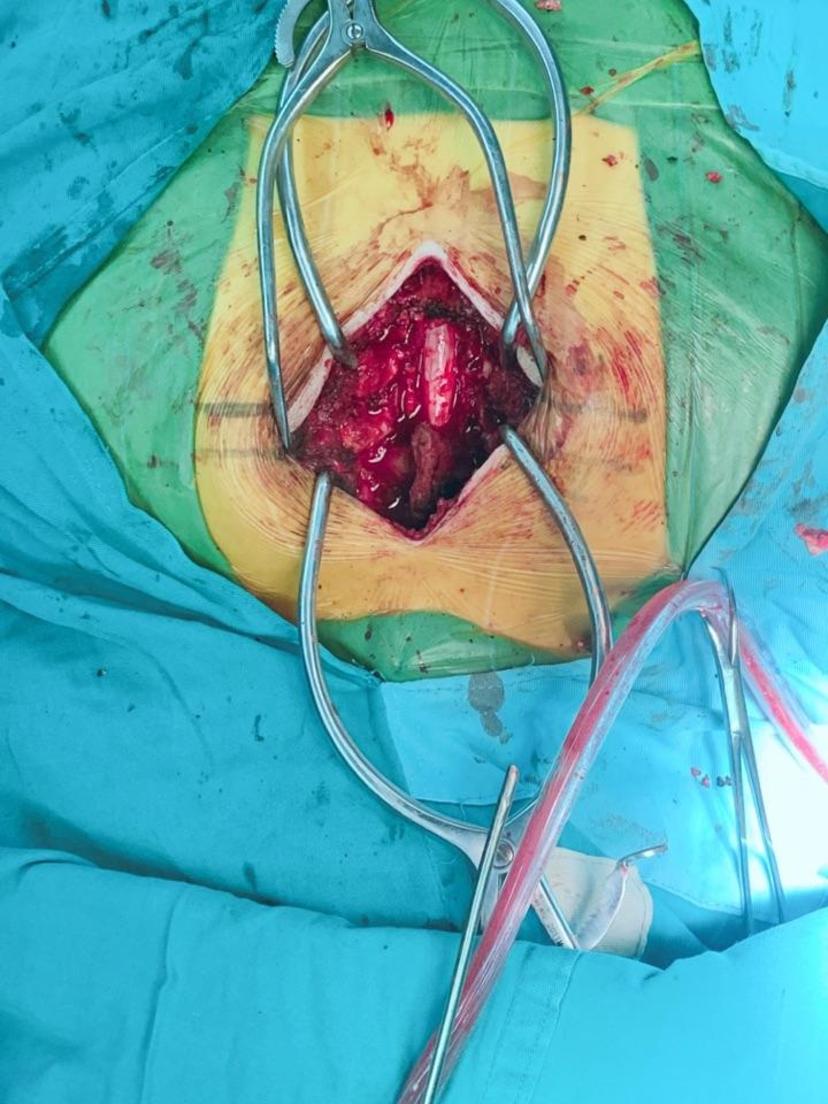

术中完全彻底减压,硬膜囊膨隆良好,恢复正常搏动